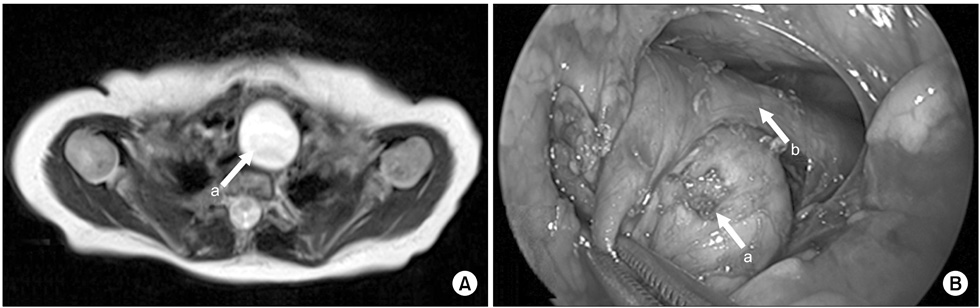

Esophageal duplication cyst of superior mediastinum. (A) There was a mass situated at just front of upper esophagus on neck MRI (2.5×2.2×4.5-cm-sized mass). (B) There was a mass at the front and right of the esophagus. Arrows: a, esophageal duplication cyst; b, true esophagus.

Fig. 4 Esophageal duplication cyst of superior mediastinum. (A) There was a mass situated at just front of upper esophagus on neck MRI (2.5×2.2×4.5-cm-sized mass). (B) There was a mass at the front and right of the esophagus. Arrows: a, esophageal duplication cyst; b, true esophagus.